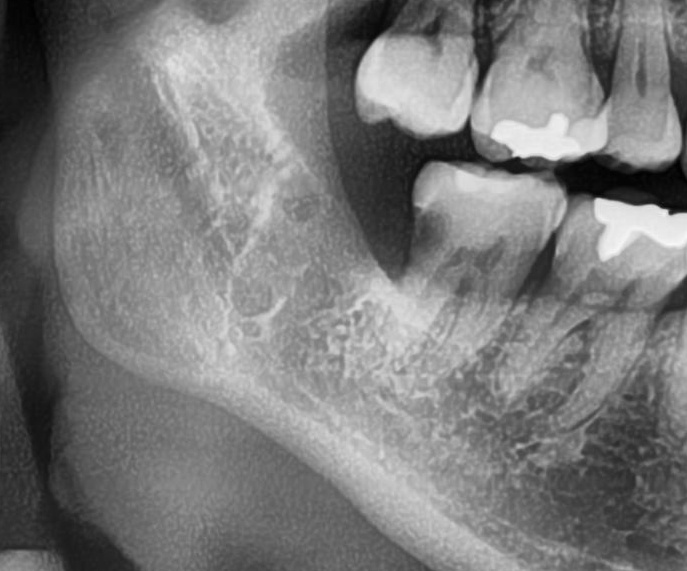

次にパノラマ写真を撮影してみると、手前の歯より低い位置でまっすぐに生えているのが確認できました。

さらに、下顎の親知らずは下歯槽神経に非常に近いところに生えている場合もあるため、CTも撮影し詳しい解析を行います。

親知らずの根っこは下歯槽神経から近い距離にありますが、抜歯は可能との診断でした。